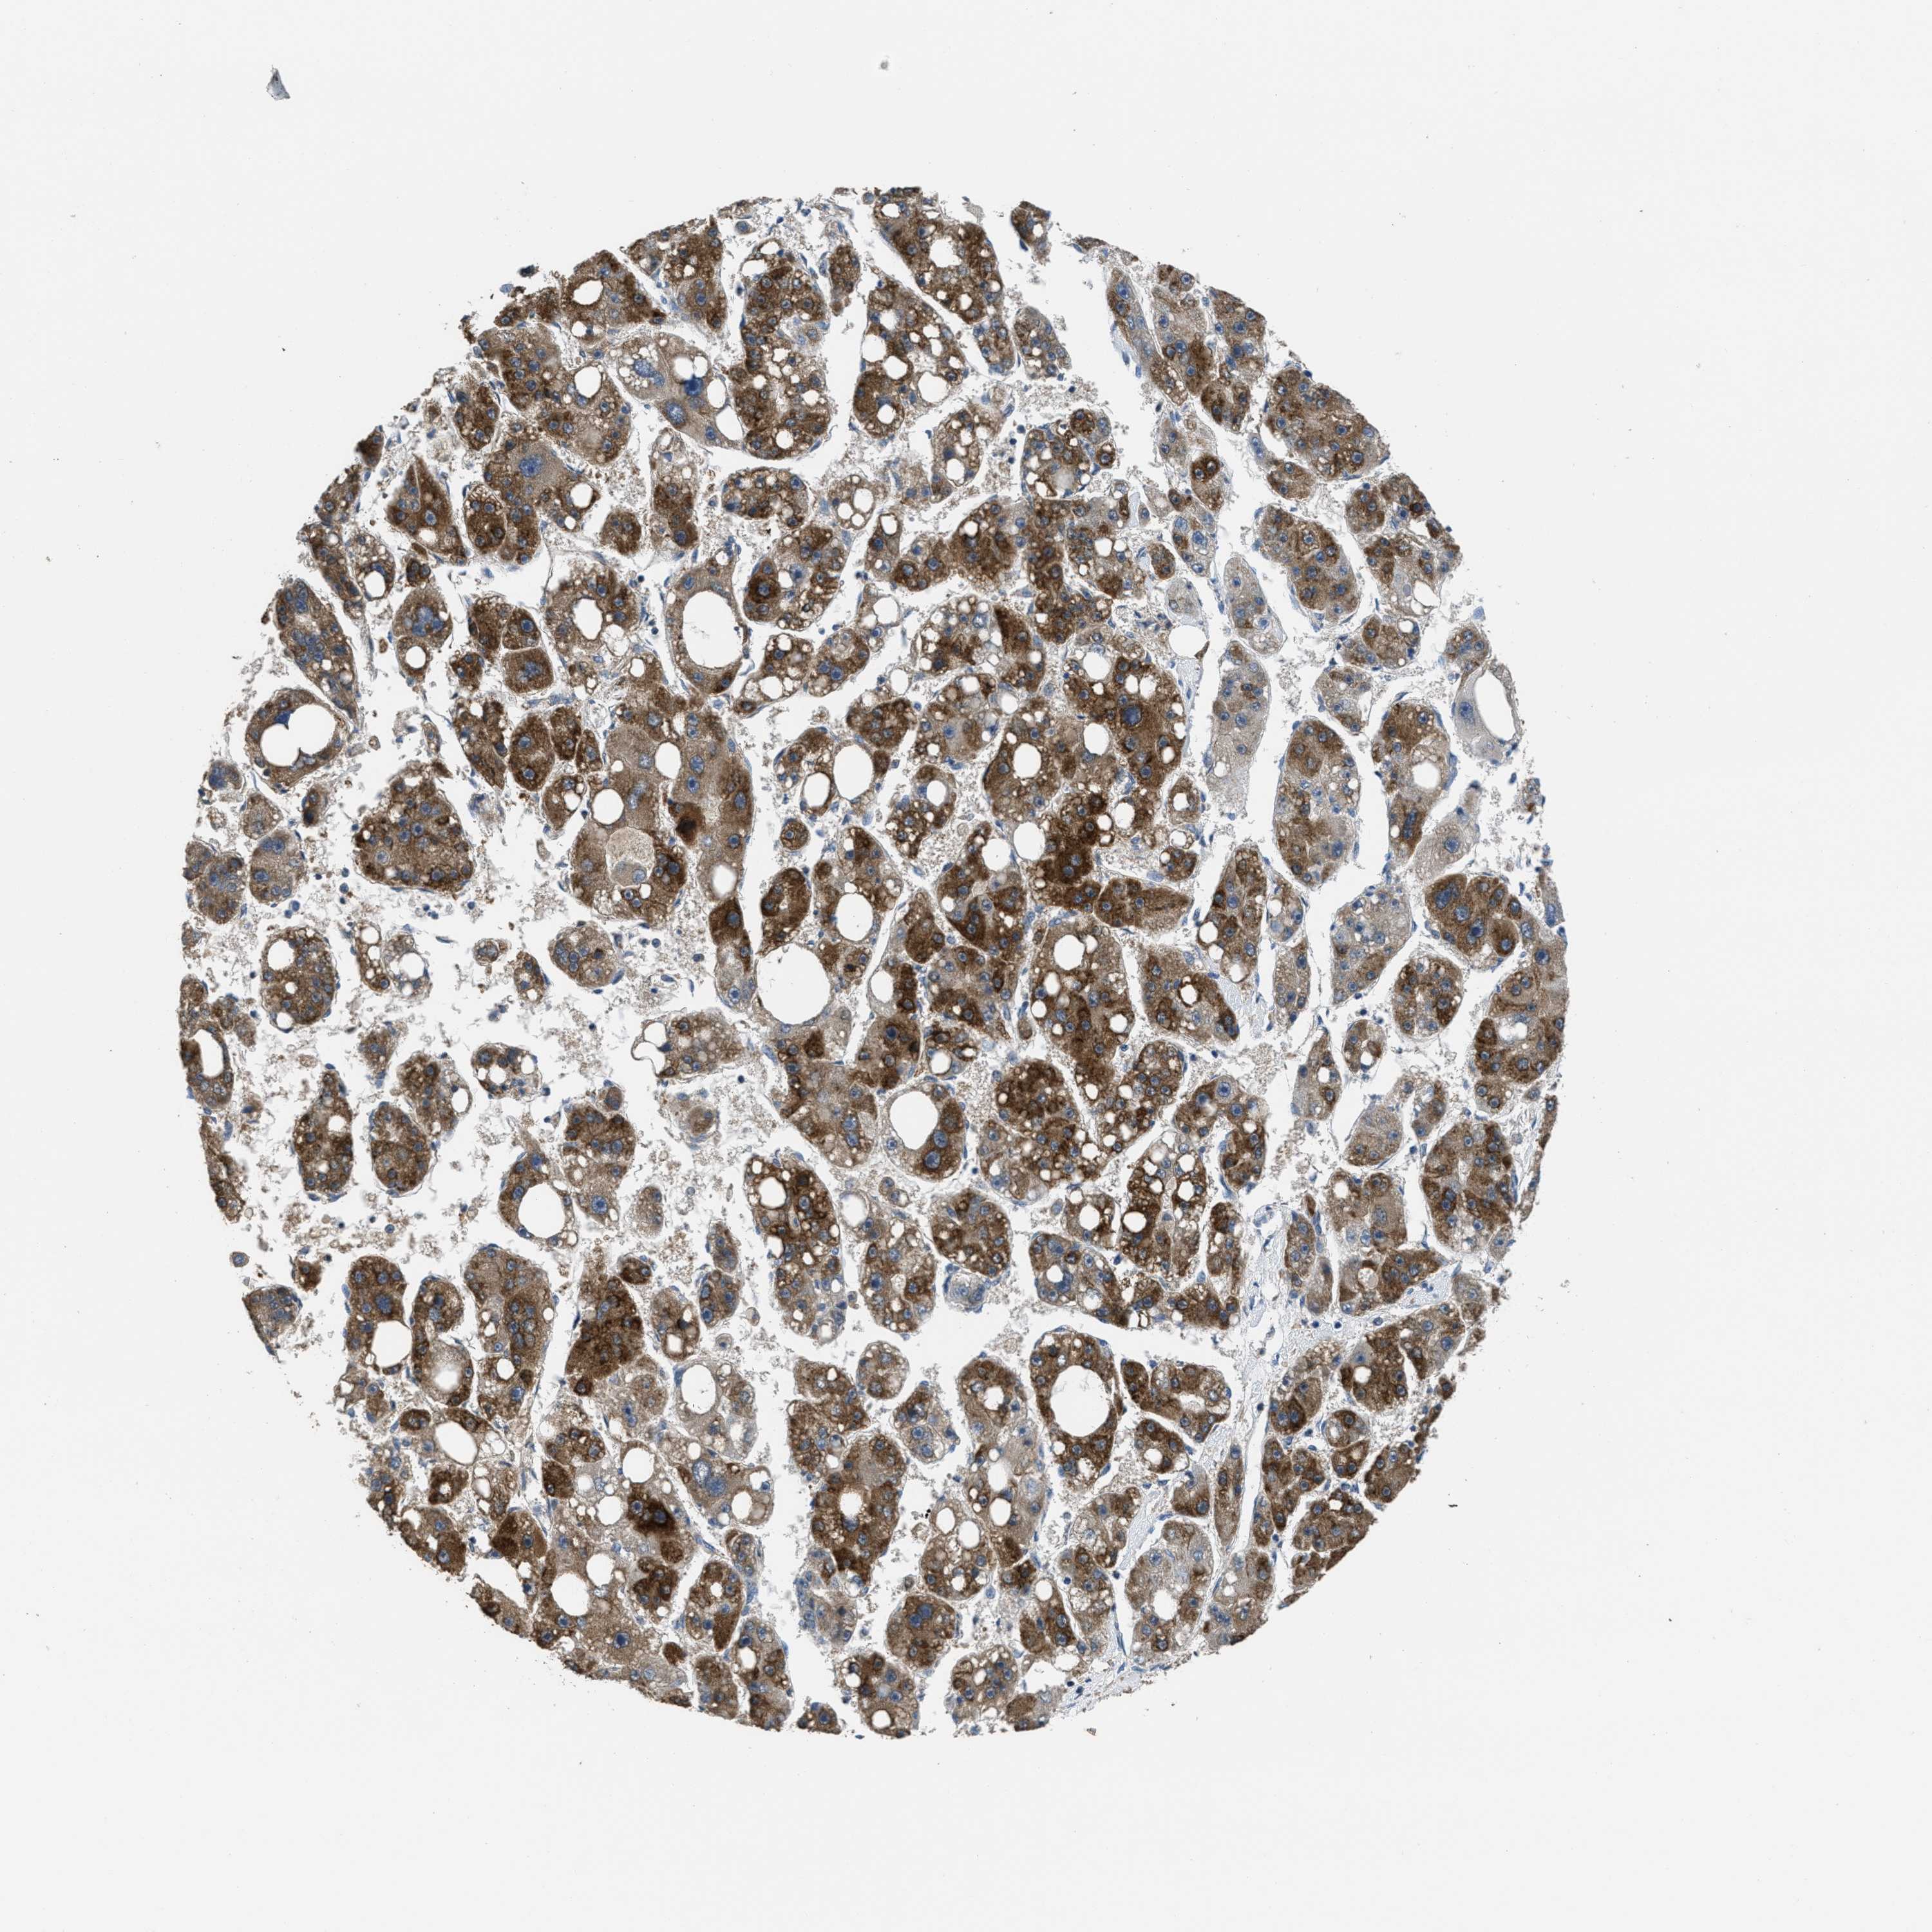

LIVER CANCER - Protein expressioni

A mouse-over function shows sample information and annotation data. Click on an image to view it in a full screen mode. Samples can be filtered based on level of antibody staining by selecting one or several of the following categories: high, medium, low and not detected. The assay and annotation is described here.

Antibody stainingi

Antibody staining in the annotated cell types in the current human tissue is reported as not detected, low, medium, or high, based on conventional immunohistochemistry profiling in selected tissues. This score is based on the combination of the staining intensity and fraction of stained cells.

Each image is clickable and will lead to virtual microscopy that enables deeper exploration of all samples and also displays staining intensity scores, fraction scores and subcellular localization as well as patient and tissue information for each sample.

Antibody HPA043704

Antibody CAB017782

Staining

High

Medium

Low

Not detected

Intensity

Strong

Moderate

Weak

Negative

Quantity

>75%

75%-25%

<25%

None

Location

Nuclear

Cytoplasmic/membranous

Cytoplasmic/membranous,nuclear

Cholangiocarcinoma

Carcinoma, Hepatocellular, NOS